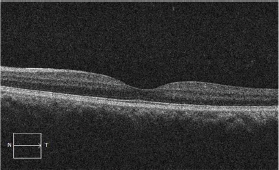

At six month follow up, the patient s visual acuity had returned to 20/20 with complete resolution of the intraretinal lesions. However, he complained of a persistent para central scotoma which was demonstrated using Amsler grid, and confirmed with 10-2 Humphrey Visual Field. OCT of the right eye showed a small area of sub foveal RPE irregularity despite resolution of the macular edema.

Figure 4: OCT OD at 6 month follow up showing complete resolution of the intraretinal fluid with subtle sub foveal RPE irregularity.